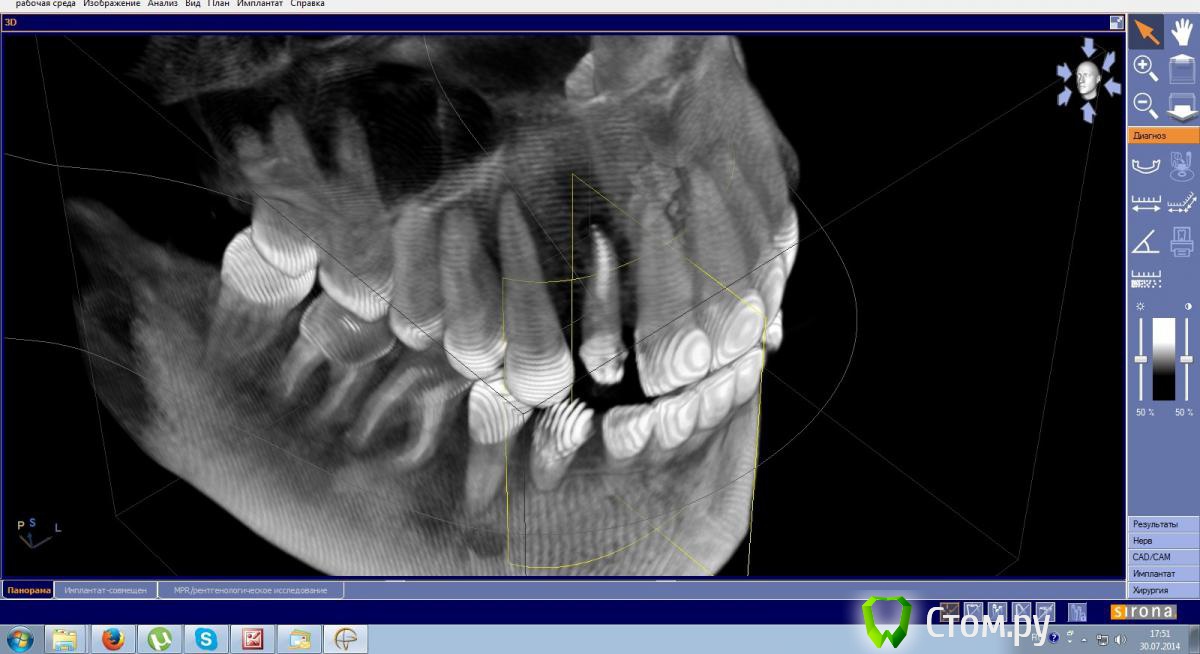

Эндж Опубликовано 30 июля, 2014 Поделиться Опубликовано 30 июля, 2014 Здравствуйте! Прокомментируйте, пожалуйста состояние моих зубов. Сейчас после ортодонтии и имплантации ношу пока времянки, через неделю планируется установка постоянных. Я вижу на двойке сверху гранулемуи мне кажется, что она увеличилась. Мой ортопед говорит, что канал хорошо пролечен и лучше не трогать, а я переживаю, что после установки постоянной коронки может начаться какая-нибудь проблема.Канал перелечили два с половиной года назад. Снимки:1) до перелечивания2) год назад3) и 4) вчера Ссылка на комментарий

Cleric Опубликовано 2 августа, 2014 Поделиться Опубликовано 2 августа, 2014 Спасибо, что ответили, да, делали в хорошей клинике, вроде должно было быть по современному протоколу, а на снимке этого не видно?. Резекцию проводит хирург?минимум, который должен был быть использован и вы это могли прочувствовать:1. коффердам - латексная завеса, изолирующая зуб от полости рта2. обильное промывание гипохлоритом натрия - должны были почувствовать запах хлорки Если этого не было, значит можно попробовать перелечить. Если было, то апикальная хирургия с последующим ретроградным пломбированием. 2 Ссылка на комментарий

Эндж Опубликовано 5 августа, 2014 Автор Поделиться Опубликовано 5 августа, 2014 минимум, который должен был быть использован и вы это могли прочувствовать:1. коффердам - латексная завеса, изолирующая зуб от полости рта2. обильное промывание гипохлоритом натрия - должны были почувствовать запах хлорки Если этого не было, значит можно попробовать перелечить. Если было, то апикальная хирургия с последующим ретроградным пломбированием.Коффедарма точно не было, а про запах хлорки не помню. А по снимку не видно качественно пролечен или нет? Ссылка на комментарий

red_butler Опубликовано 5 августа, 2014 Поделиться Опубликовано 5 августа, 2014 Коффедарма точно не было, а про запах хлорки не помню. А по снимку не видно качественно пролечен или нет?по снимку нормально пролечен. Соглашусь с M@estro -делать резекцию апекса Ссылка на комментарий